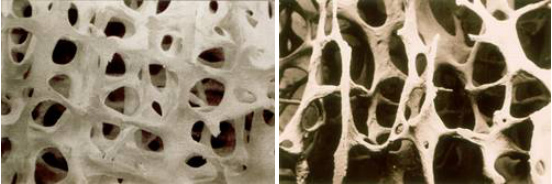

骨质疏松症(Osteoporosis, OP)是一种以骨量低下,骨微结构破坏,导致骨脆性增加,易发生骨折为特征的全身性骨病(见图)。其一直被认为是老年人特有疾病的骨质疏松症,实际上在儿童时期就已存在。

正常骨与骨质疏松症骨结构的不同

正常骨 骨质疏松症